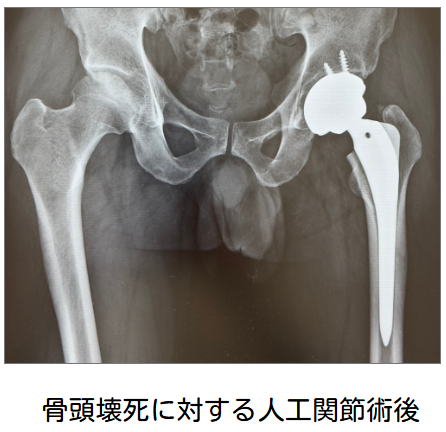

一方、比較的若年で、病期がStage 3Bまでであれば、関節温存手術が検討されることがあります。手術には、骨切り術や骨移植術などの関節温存手術と、人工骨頭置換術(BHA)や人工股関節全置換術(THA)などの非温存手術があります。実際の術式は、年齢、病期、病型だけでなく、職業、生活様式、家庭環境なども踏まえて総合的に決定されます。

壊死した部分が荷重部に広く及ぶほど、骨頭圧潰の危険性は高くなります。そのため、圧潰の可能性が低いType Aでは経過観察が選択されることが多く、圧潰の可能性が高いType Cでは関節温存手術が検討されます。Type Bはその中間に位置し、慎重な経過観察が必要です。すでに圧潰が進行している場合や、骨頭の温存が難しい場合、関節症性変化が強い場合には、THAやBHAが適応となります。

特発性大腿骨頭壊死症は、比較的若く活動性の高い年代に発症することが多いため、将来的な再手術の可能性も見据えて治療法を選択することが大切です。当院では手術は行っておりませんが、連携する専門医療機関をご紹介しています。なお、手術後のリハビリテーションについては、当院で継続して行うことが可能です。